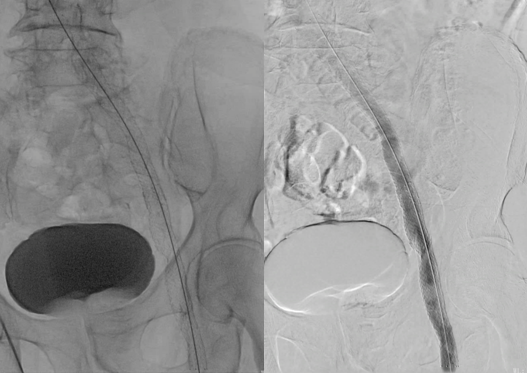

球囊扩张后支架定位,透视下释放14×140mm支架2枚,术后评估支架扩张良好,支架头端定位伸入下腔静脉5mm左右,未覆盖右侧髂总静脉开口。